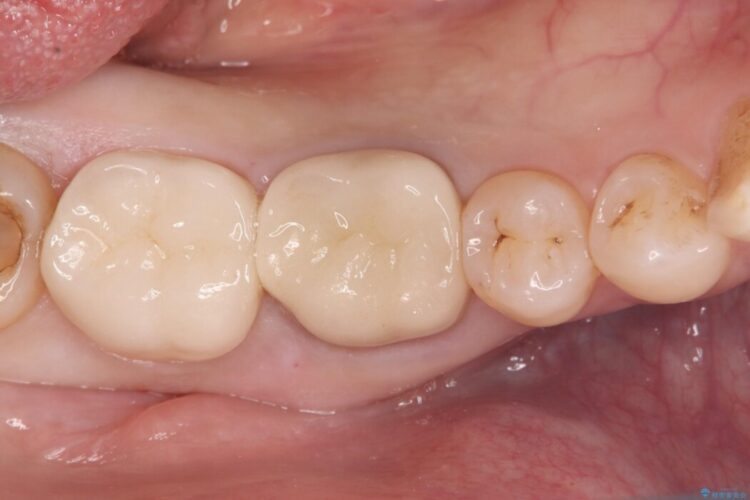

古い銀歯と中の虫歯をしっかりと取り除き、耐久性の高いセラミッククラウンで補強しました。

セラミックは見た目が美しいだけでなく、汚れがつきにくく、良好な口腔衛生状態を維持しやすくなり長期的に安心して使用できる状態へと整えることができました。